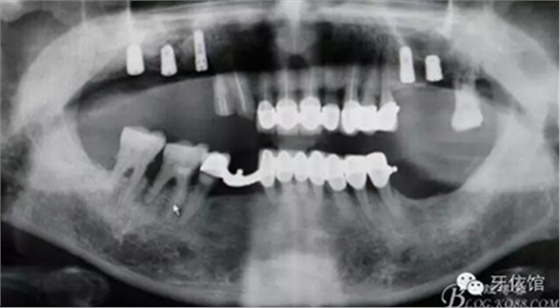

5,6,7擴(kuò)孔

植入植體同時GBR

縫合

術(shù)后X光片

病例圖片較多,較詳細(xì)地闡述了改良式外提升技術(shù)的步驟,自我感覺這種開窗方式更加安全可靠,希望我的這個病例能夠?yàn)檎跍?zhǔn)備做外提升但又不敢貿(mào)然行動的老師們有所幫助。